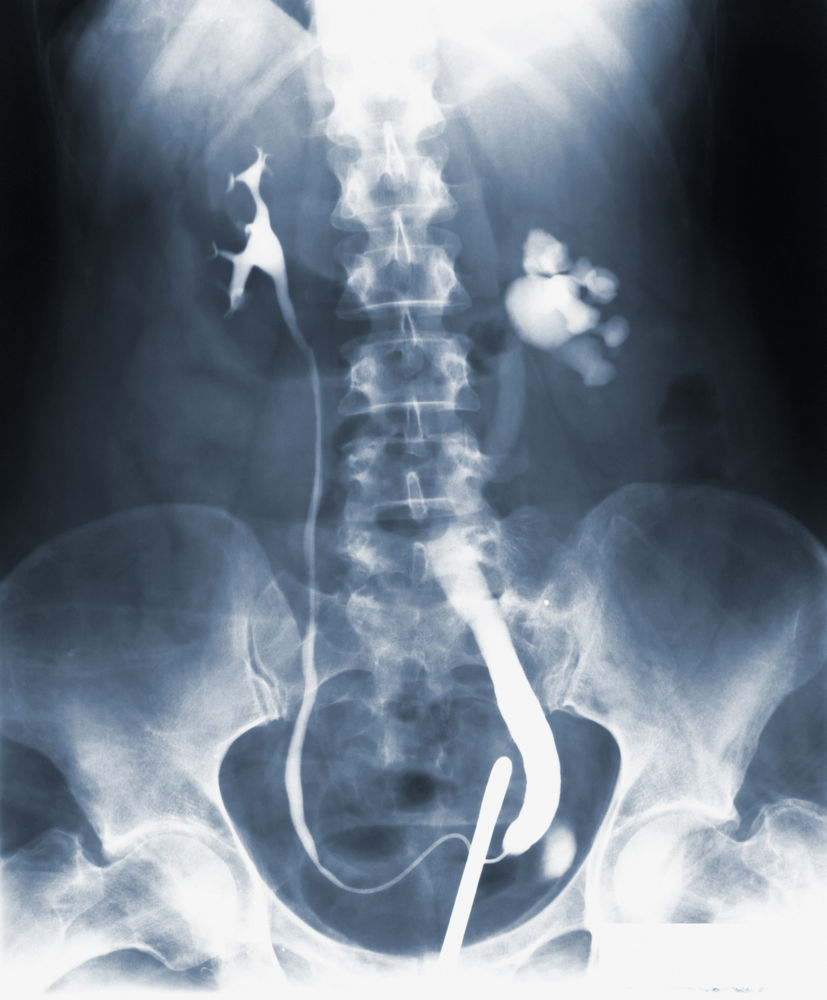

(PDF) Estimation of Heights and Body Masses of Tuberculosis Patients in the Canadian Fluoroscopy

Estimated average body masses for age for Canadian tuberculosis... Download Scientific Diagram